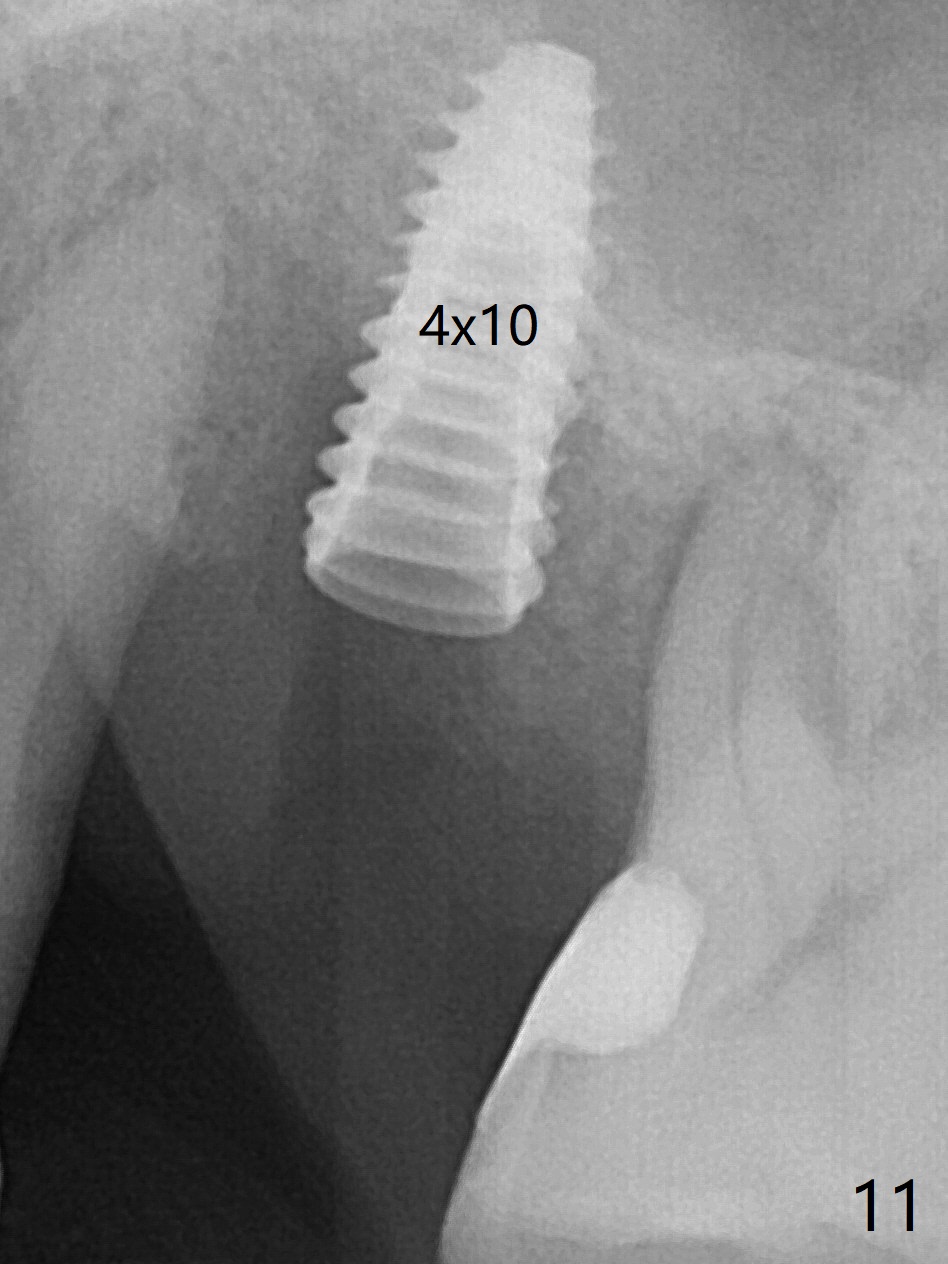

There is more bone apical to the residual root at #13 (Fig.1 red line). An immediate implant along the long axis of the root can be longer, 11.5 mm, favorable for primary stability (Fig.2 (CT taken immediately preop)). The initial trajectory is not ideal (Fig.3). When the pointed/Lindamann bur is removed (Fig.4), effort is made to move the apical end of the osteotomy distal (Fig.5 red arrow) by removing the apical bone (red dashed line). Following sequential osteotomy, a 4x10 mm dummy implant is placed with the trajectory remaining not so ideal (Fig.6,7). As the dummy implant is removed (Fig.8), a new osteotomy is established distal to the existing one (Fig.9). Subsequent drills gradually shift into the original osteotomy (Fig.10 red arrow). When the same dimension dummy implant returns, the trajectory improves with decreased stability (Fig.11). It seems reasonable to place a larger implant without further osteotomy. After placing PRF membrane and Vanilla graft for sinus lift (Fig.13 *), a 4.5x10 mm definitive implant is placed with loss of control in the trajectory (Fig.12,13).

When the initial osteotomy is off substantially (Fig.4), an osteotomy should be established de novo and as early as possible (Fig.14) so that subsequent osteotomy will not relapse to a great extent. More ideally, the initial osteotomy should be planned correctly (Fig.15,16) with sacrifice of the bone height. Nearly 1 month postop, the 4.5x5.5(5) cementation abutment is loose. When it is removed, the patient feels pain from the implant. A 5.5x6 mm healing abutment is placed instead. The implant osteointegrates with trabecular pattern in the sinus 9 months postop (Fig.20 *). The gingiva around the crown at #13 is healthy 1 year 4 months post cementation (Fig.18). Check the distal surface of #13 for bone loss if the tooth #14 is to be extracted.